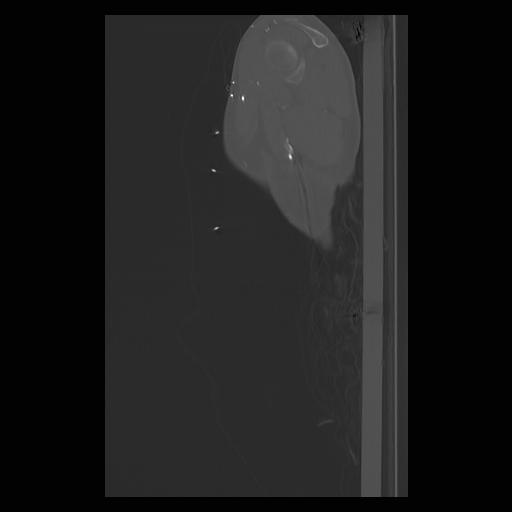

33 PULMON,CE,Sagittal,3.000,PULMON,Sagittal,